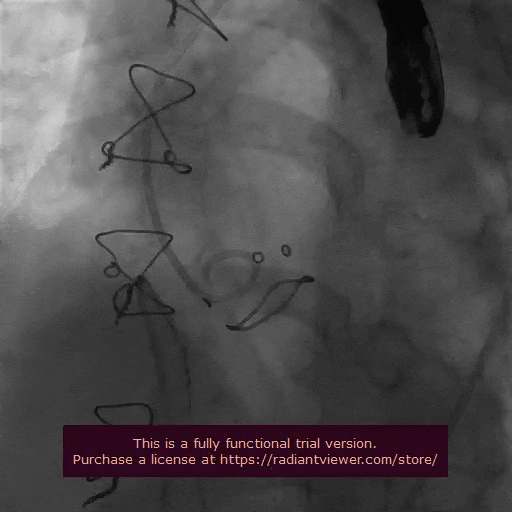

术中精彩操作

冠脉造影

导丝跨瓣

球囊预扩

瓣膜初始定位

完全释放,瓣膜形态良好,无周漏